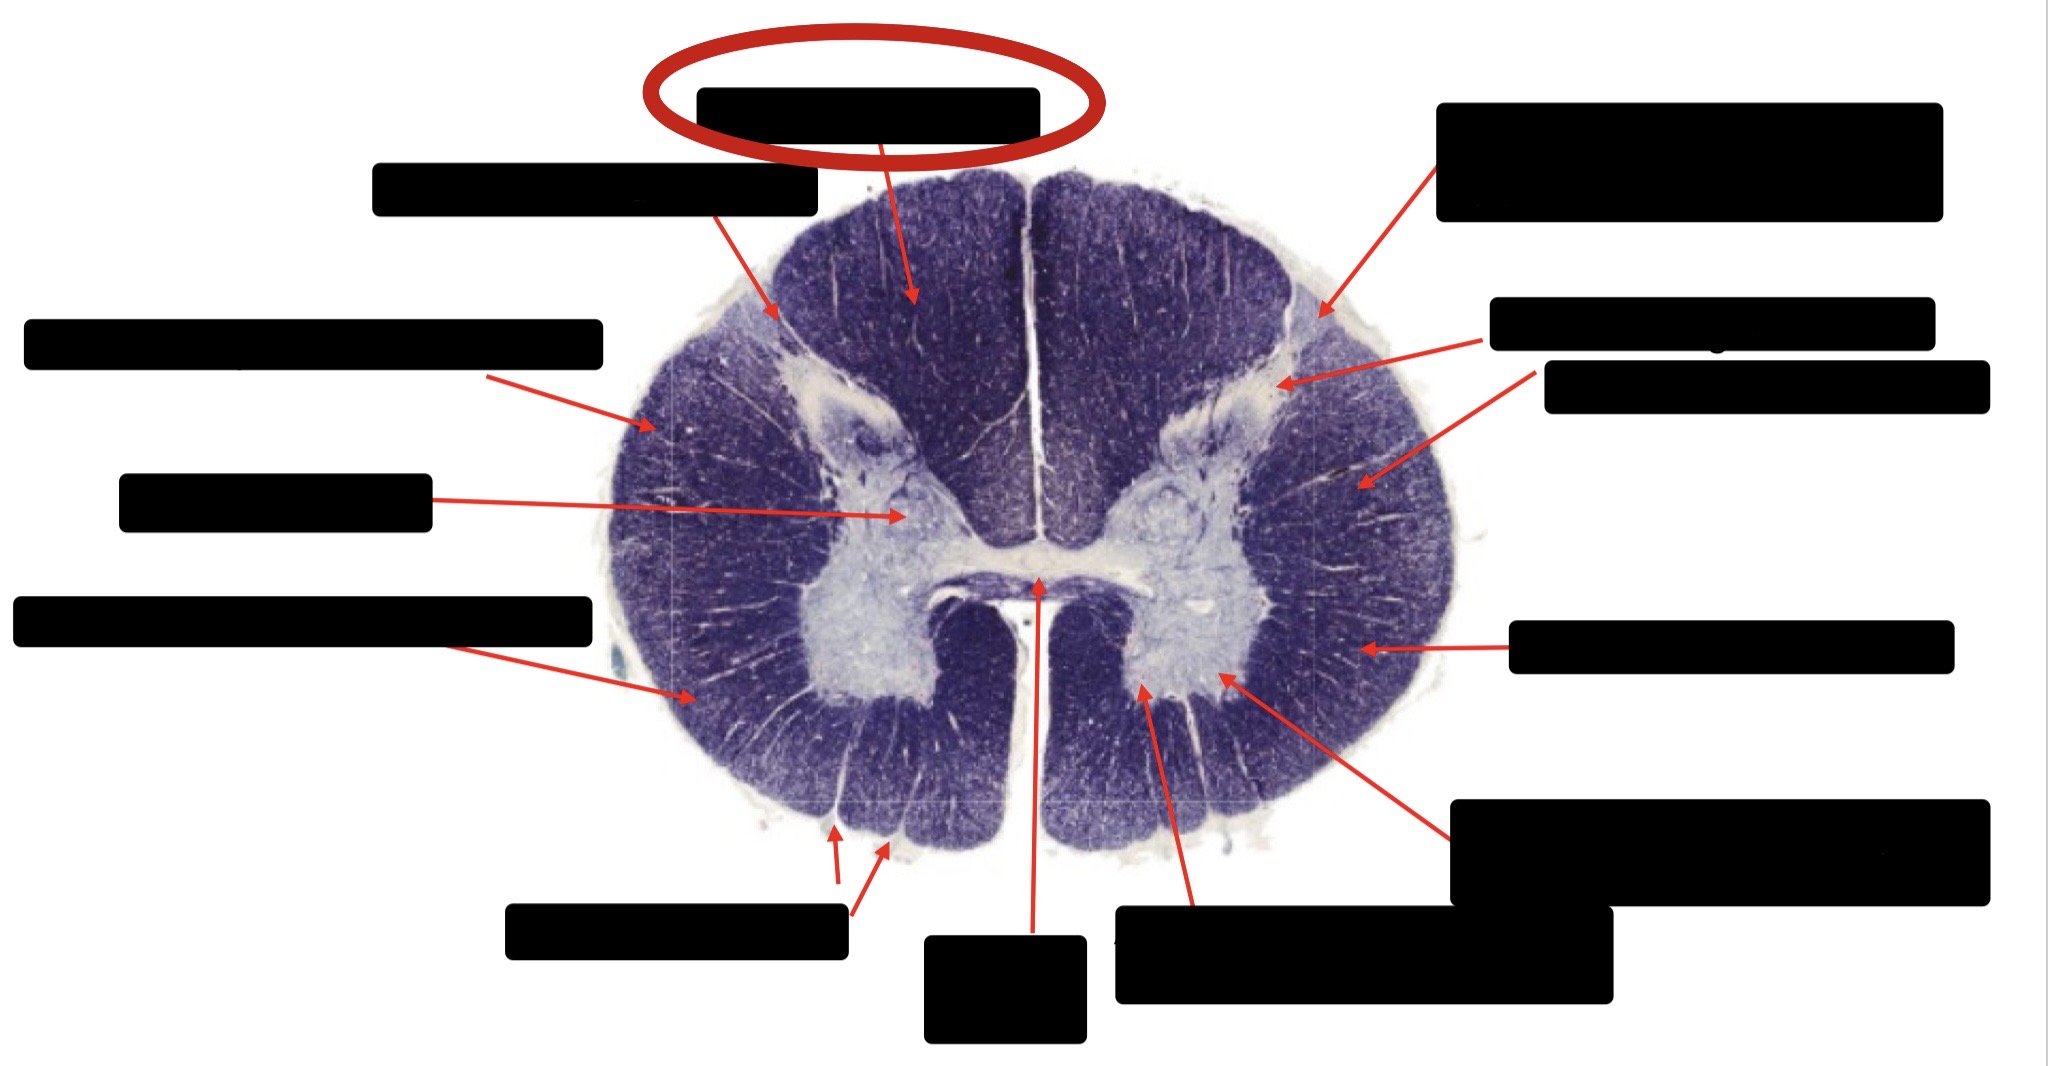

Posterior Columns (Joint Position, Vibration, Pressure)

Fasciculus Cuneatus

Fasciculus Gracilis

Dorsal Root

Dorsal Spinocerebellar Tract

Ventral Spinocerebellar Tract

Lateral Spinocerebellar Tract (Pain & Temperature)

Ventral Root

Anterior Horn (Motor Neurons)

Distal Limb Movements

Lateral Corticospinal (Pyramidal Tract)

Rubrospinal Tract

Axial & Proximal Limb Movements

Lateral Reticulospinal Tract

Vestibulospinal Tract

Ventral Reticulospinal Tract

Tectospinal Tract

Ventral Spinthalamic Tract (Pressure Touch - Minor Role)

Ventral (Uncrossed) Corticospinal Tract (Distal Limb Movements - Minor Role)